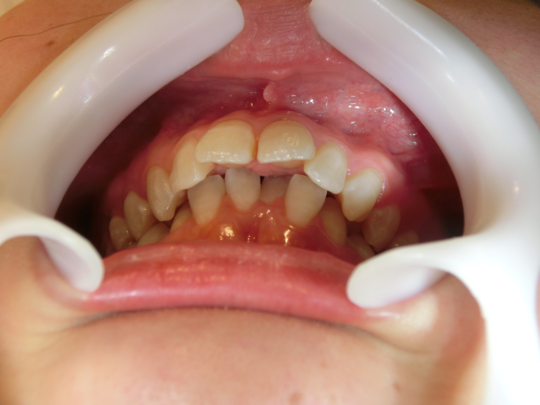

治療前

治療説明 歯科矯正でも目立ちにくい矯正方法であるマウスピース矯正で治療しました

治療期間 2年6か月

治療費用49,8000 円